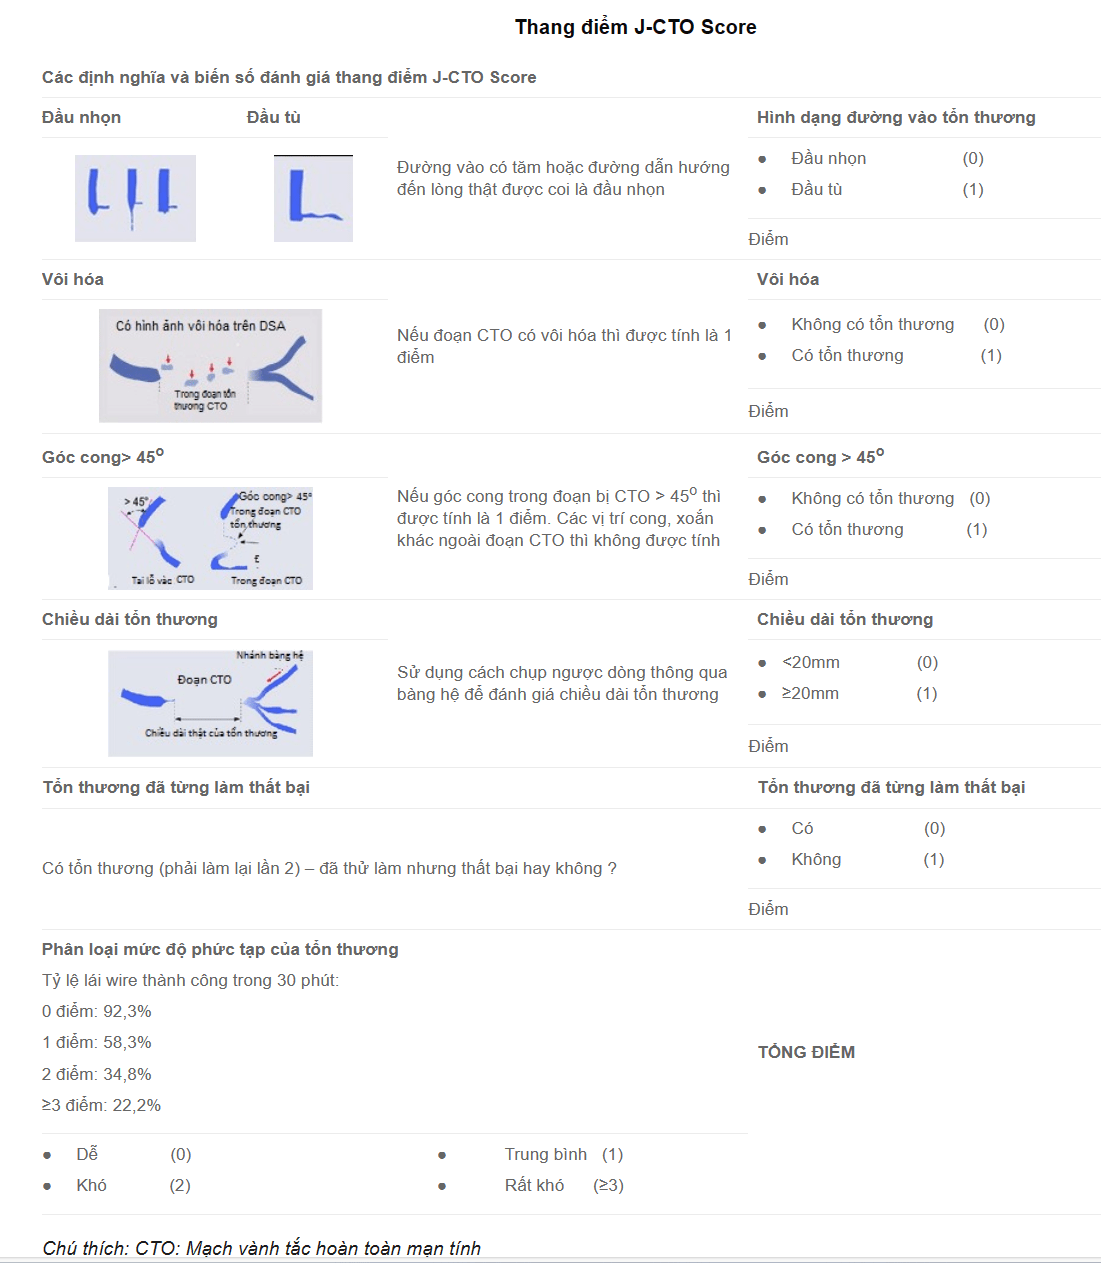

Dụng cụ

Kim Ross thưở ban đầu đã được cải tiến bởi Brockenbrough bằng cách giảm đường kính kim từ 18G -> 21G ( ở 1,5 cm đầu xa). Điều này mang lại sự an toàn cao hơn trong trường hợp kim đâm ra bên ngoài khoang nhĩ trái.

Kim Brockenbrough (Medtronic, Minneapolis, Minnesota) chỉ có một kích cỡ. (hình 1A)

Một số hãng sản xuất Kim xuyên vách với các độ cong khác nhau chẳng hạn như dòng BRK (St. Jude Medical, St Paul, Minnesota). (Hình 1B)

Khử trùng lại (hấp lại) không được khuyến nghị do lòng kim dài, khó vệ sinh.

Các loại ống bao (sheath) gốc cong cố định thường được sử dụng: ống bao Mullins (Hình 2), ống thông Swartz (Hình 3).

Hệ thống kim đôi đồng trục xuyên vách Endrys (Cook Europe, Bjaeverskov) được một số người sử dụng, đặc biệt khi có nhĩ trái nhỏ. Lòng ống rất nhỏ được cho là sẽ cải thiện sự an toàn.(Hình 4A, B)

Hệ thống kim xuyên vách NRG (Baylis Medical, Montreal) sử dụng tần số vô tuyến. Khi xác định vị trí tối ưu, sử dụng tần số vô tuyến, giúp đầu kim tù đi qua vách ngăn. Kim NRG có nhiều hình dạng khác nhau. (Hình 5A, B)